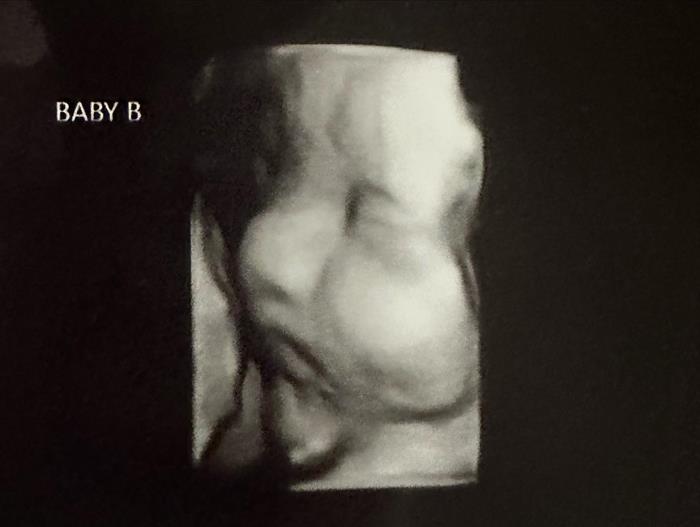

เคลซีย์เผยภาพอัลตราซาวด์ที่น่าทึ่ง แสดงให้เห็นชัดว่าเธอมีมดลูก 2 มดลูก และภายในนั้นก็มีทารก 2 คนอยู่แยกกัน โดยทั้งคู่เป็นเพศหญิง และเมื่อเร็ว ๆ นี้เธอได้ผ่านการตรวจประเมินสุขภาพของทารกในครรภ์และพบว่า ทารกทั้ง 2 ครรภ์มีสุขภาพแข็งแรง "ใบหน้าเล็ก ๆ ของพวกเขาน่ารักไหม ? คิดว่าจะคล้ายกันไหม ? ฉันรู้สึกว่าพวกเขาจะแตกต่างกันอย่างสิ้นเชิง" เคลซีย์ กล่าว